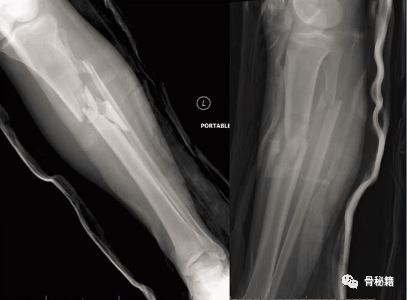

很有可能,你的髓内钉植入近端1/3的时候是这样……

近端1/3骨折,尤其是前后斜行的骨折线时,你插入髓内钉以后,经常会形成近端后倒。

近端1/3的髓腔很大,胫骨干中部才有狭窄的管腔,可以控制髓内钉,远端也是属于较大的髓腔,比较难控制。

看下面的病例,胫骨干中部比较稳定,而远端则形成了摆动效应,十分不稳定,就是传说中的“筷子搅大缸”